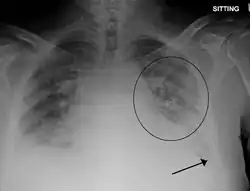

| Pulmonary edema with small pleural effusions on both sides | |

Chest X-ray has been used for many years to diagnose pulmonary edema due to its wide availability and relatively cheap cost.[4] A chest X-ray will show fluid in the alveolar walls, Kerley B lines, increased vascular shadowing in a classical batwing peri-hilum pattern, upper lobe diversion (biased blood flow to the superior parts instead of inferior parts of the lung), and possibly pleural effusions. In contrast, patchy alveolar infiltrates are more typically associated with noncardiogenic edema.[3]